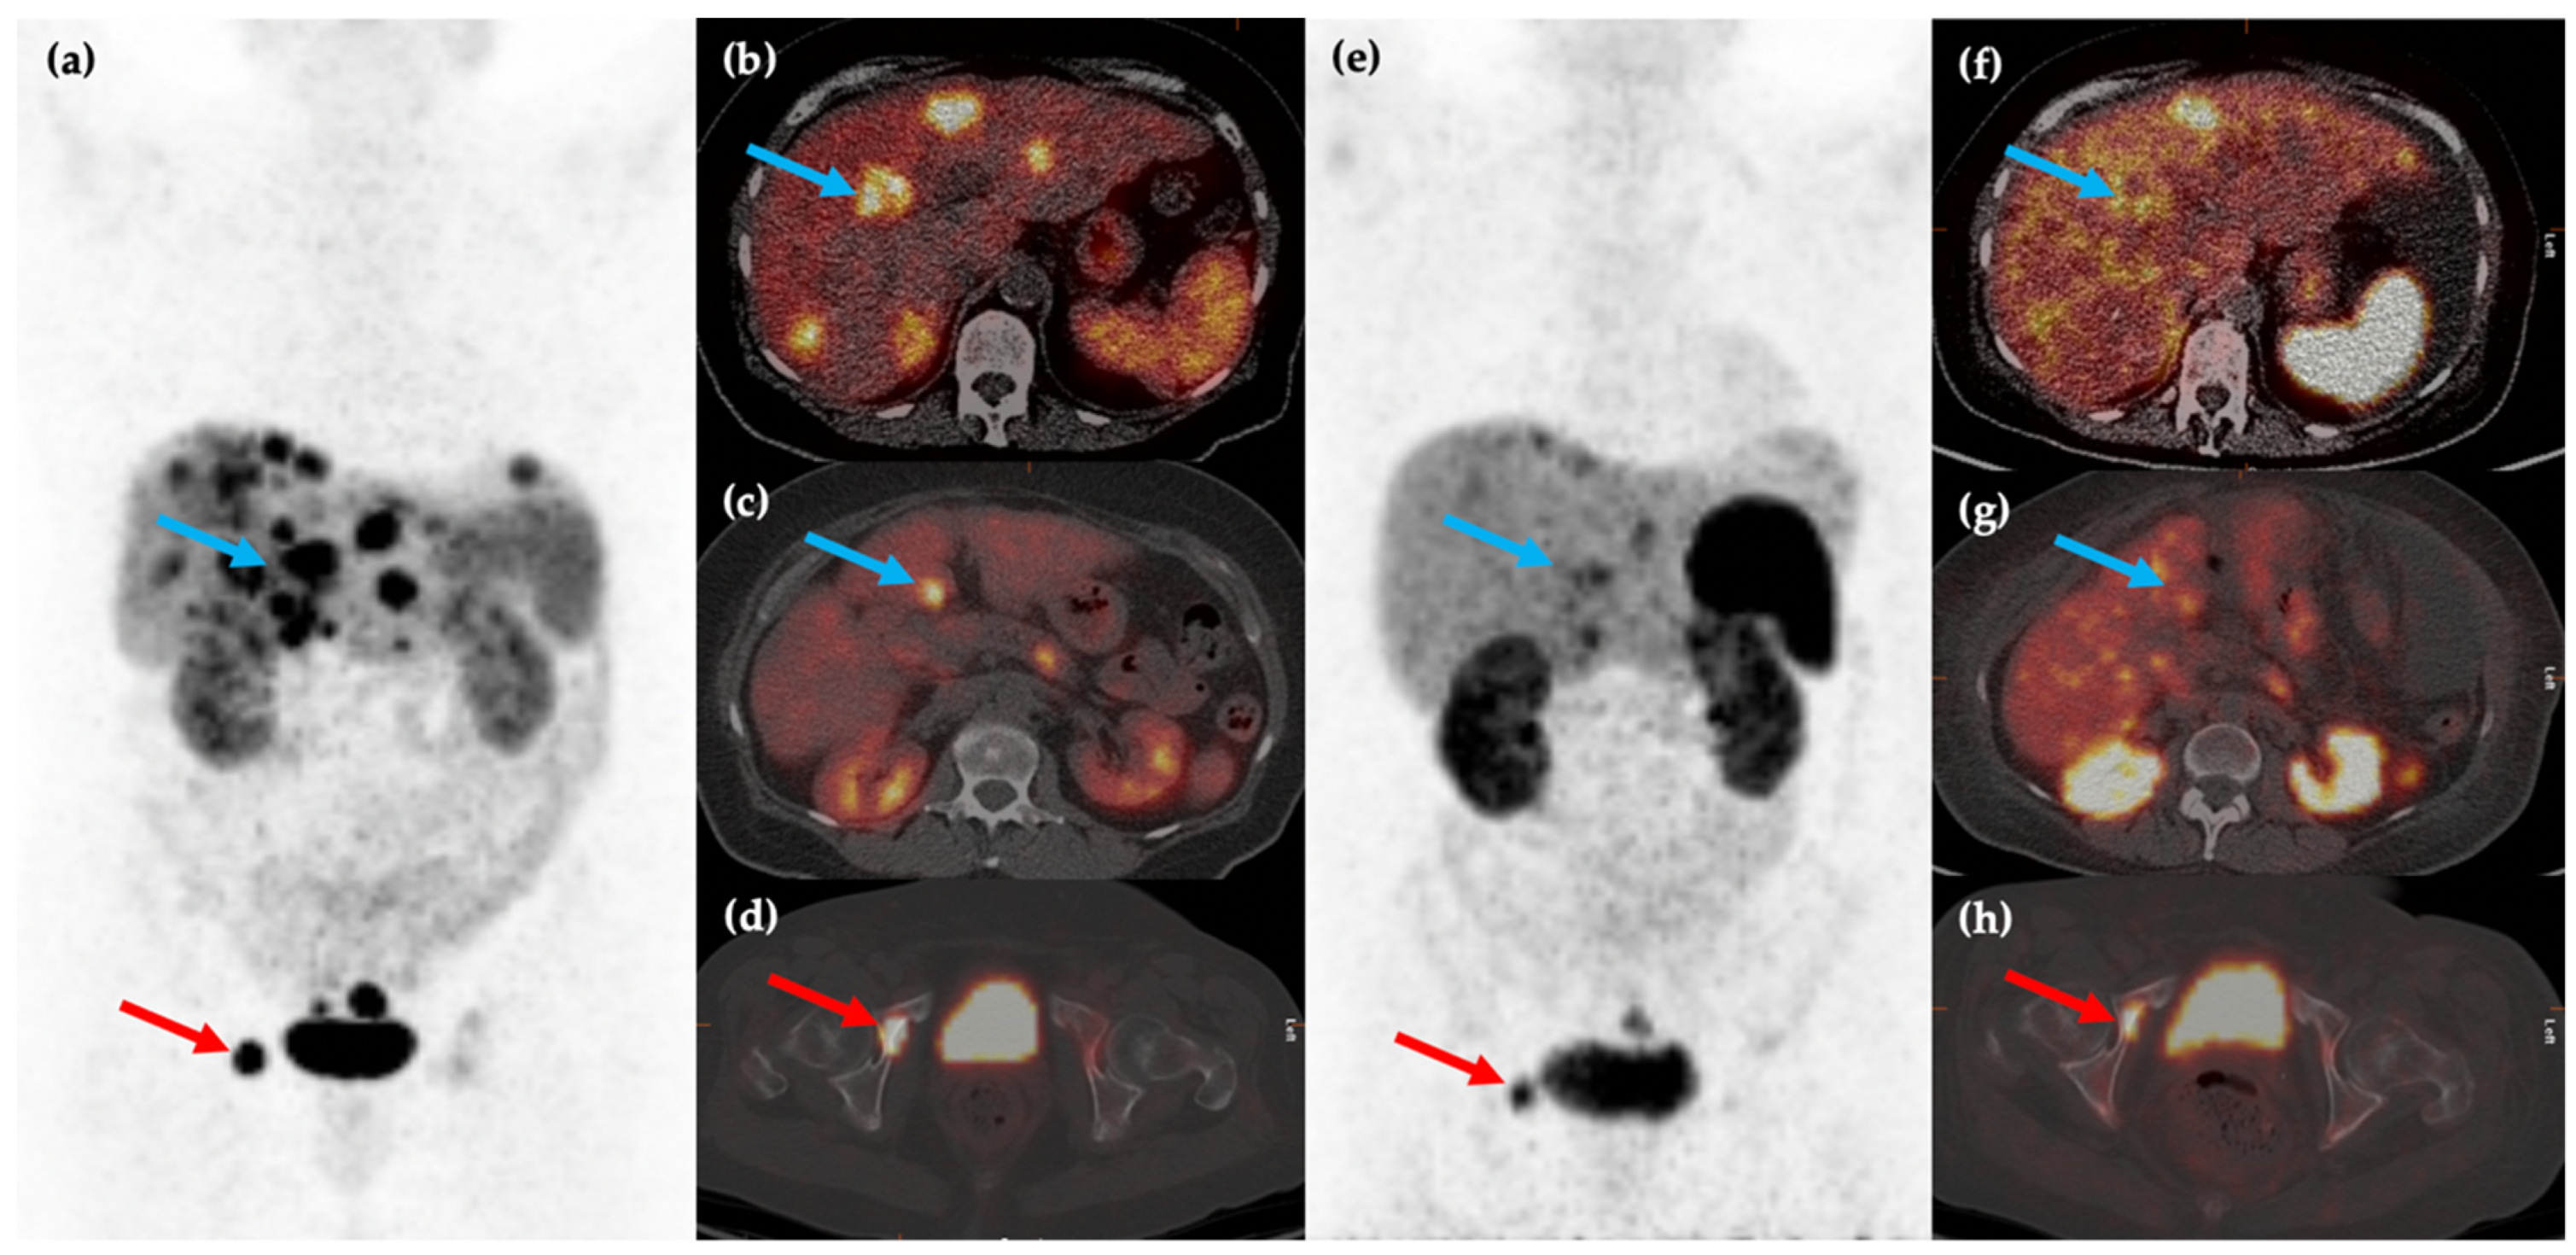

The application of the macrocyclic chelator DOTA (1,4,7,10-tetraazacyclododecane-1,4,7,10-tetraacetic acid) paved the way for use of positron emission tomography to image NENs, by combining it with positron emitter Gallium-68 (68Ga) and labelling this compound with somatostatin analogues to produce tracers collectively known as 68Ga-DOTA-peptides. 68Ga- DOTA-Tyr3-ocreotide (68Ga-DOTATOC) was the first tracer to show utility in imaging of NEN in 2001 [24], followed soon after by 68Ga-DOTA-Tyr3-octreotate (68Ga-DOTATATE) and 68Ga-DOTA-1-NaI3-octreotide (68Ga-DOTANOC) [25]. Positron emission tomography (PET) imaging using DOTA-conjugated somatostatin analogues posed several advantages, with higher spatial resolution and better image quantification with PET over SPECT (Figure 1) [26], and a higher affinity profile to SSTR of 68Ga-DOTA-peptides compared with 111In-DTPA-octreotide [27] which in turn improves detection of smaller lesions or those with lower SSTR expression [28]. Practical advantages include faster image acquisition, lower radiation dose [29], a longer half-life and better commercial availability of Germanium-68/Gallium-68 generators [30].

Figure 1.

58-year-old male with a history of rectal bleeding and a mesenteric mass identified on conventional CT imaging. 68Ga-DOTATATE PET/CT maximum intensity projection (MIP) (a) and axial (b,c) images shows the somatostatin receptor (SSTR) positive lesion at the root of the small bowel mesentery (blue arrows) with improved spatial resolution compared to 111In-pentreotide SPECT/CT ((d–f), red arrows).